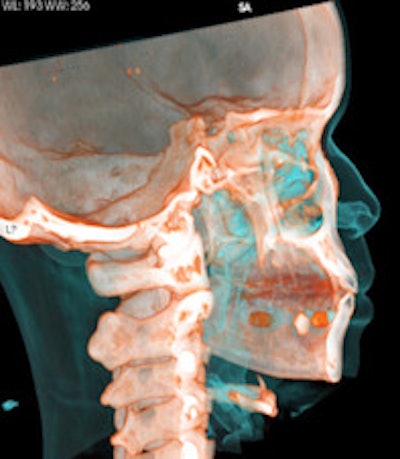

Top left: Axial plane in pulmonary window showing three pellets underneath the tongue. Top right: 3D reconstruction of an incidental finding of three sublingual cocaine pellets in a case of brawl/fist fight with subsequent CT and scan of the viscerocranium. The patient was immediately put under arrest and transferred to the affiliated custody ward. This scan was performed to rule out facial fractures sustained during the fist fight. Bottom left: Secured evidence of similar pellets (weight approximately 1 g). Bottom right: 3D reconstruction of gas-filled condom with two pouches (bags) of cocaine powder inside located in the descending colon. All images courtesy of Dr. Patricia Flach.To determine which diagnostic imaging procedures produce the best results, radiologists from Bern and Zurich compared the accuracy of different modalities in a retrospective study. They evaluated 35 CT exams, 70 digital radiography (DR) exams, and 30 low-dose linear slit digital radiography (LSDR, Lodox Systems) exams taken of 83 suspects between February 2004 and April 2011.